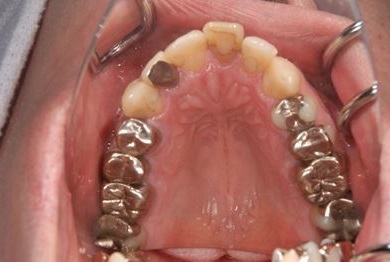

性別/年齢 男性 / 37歳

主訴 白い詰め物の修復などのメンテナンスを希望。

治療方針 セラミック治療にて、審美的回復を行う。

治療内容 オールセラミッククラウン1本(オールセラミック用土台1本)

総治療費 143,325円

治療期間 2ヶ月